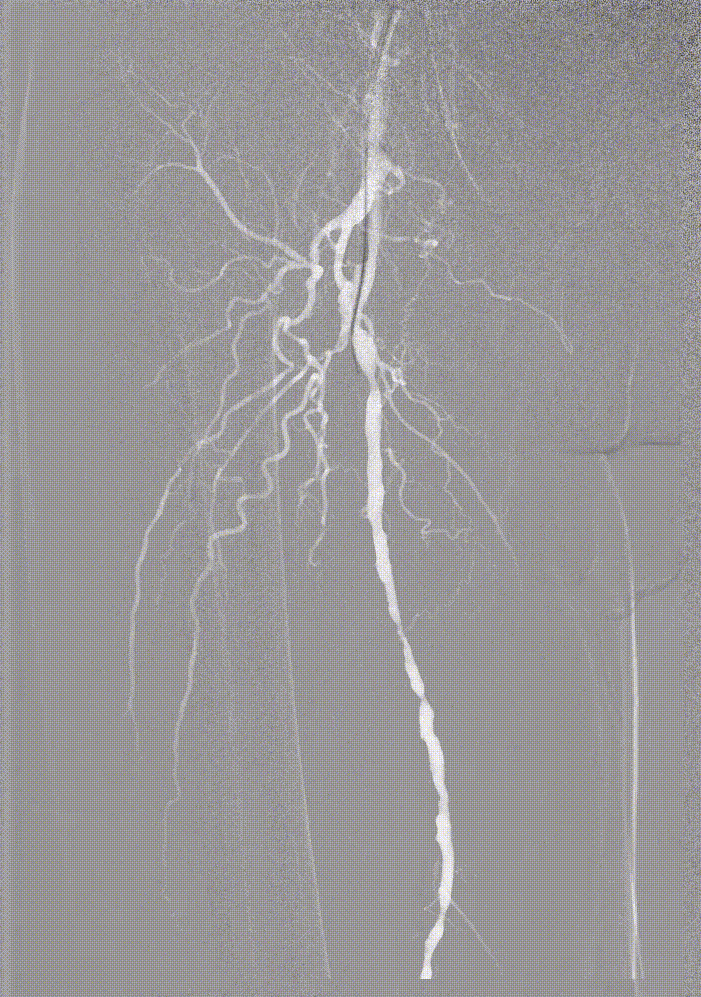

步进造影:股浅动脉起始重度狭窄、中段重度狭窄,腘动脉远端重度狭窄、胫前动脉、胫后动脉闭塞

因患者股浅动脉及腘动脉狭窄闭塞段均严重钙化,选择使用振波球囊(6mm*80mm、5mm*80mm)

分别对股浅动脉、腘动脉狭窄闭塞段扩张(球囊至4atm,3级振波强度3个循环,5级振波强度3个循环);球囊切迹逐渐消失

IVUS提示病变段仍有局部重度狭窄,遂选择最新上市的”始祖鸟”紫杉醇药物涂层球囊(5*150mm、6*150mm )对残余狭窄进行扩张

IVUS提示病变段仍有局部重度狭窄,遂选择最新上市的”始祖鸟”紫杉醇药物涂层球囊(6*150mm、 5*150mm ) 分别对股浅动脉、腘动脉、胫腓干动脉逐段扩张,压力至工作压维持3分钟。

步进造影配合血管腔内超声诊断导管提示:股浅动脉全程、腘动脉、胫腓干动脉血流通畅,未见明显夹层、造影剂外溢,远端未见栓塞,膝下动脉如前。